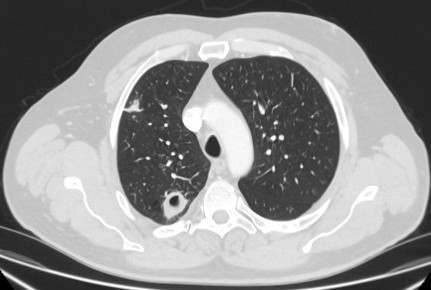

Computed tomography (CT) showing examples of malignant perifissural nodules. Note the spiculated edge of the nodules and the evident retraction of the adjacent fissure. Both resection tissue analyses confirmed adenocarcinoma of lung

From the collection of Dr George Tsaknis, MD, PhD, FRCP(London), MRQA, MAcadMEd, PGCert; used with permission